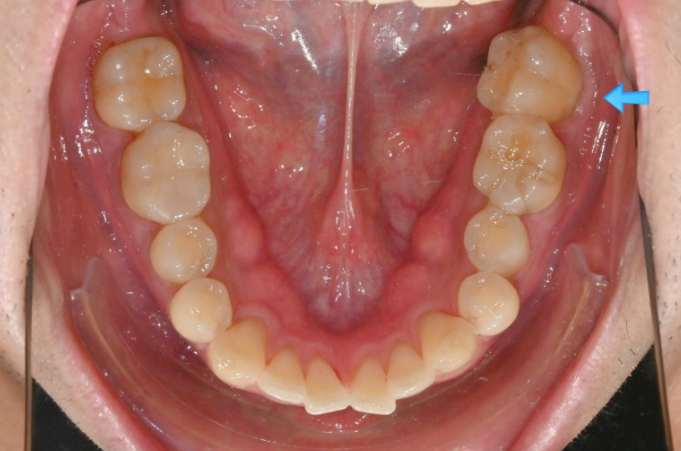

어금니가 엇갈려 교합이 안되는 상태를 가위교합 이라고 합니다.

파란 화살표와 같이 물리는 상태를 가위교합이라고 합니다.

맨 뒤 큰 어금니에 흔하게 보이는 부정교합입니다.

위 어금니는 배열에서 바깥으로 나가있고

아래 어금니는 안으로 쓰러져 있습니다.

경미한 총생과 중심선 불일치, 가위교합, 벌어짐, 과개교합 문제가 있는 상황입니다.